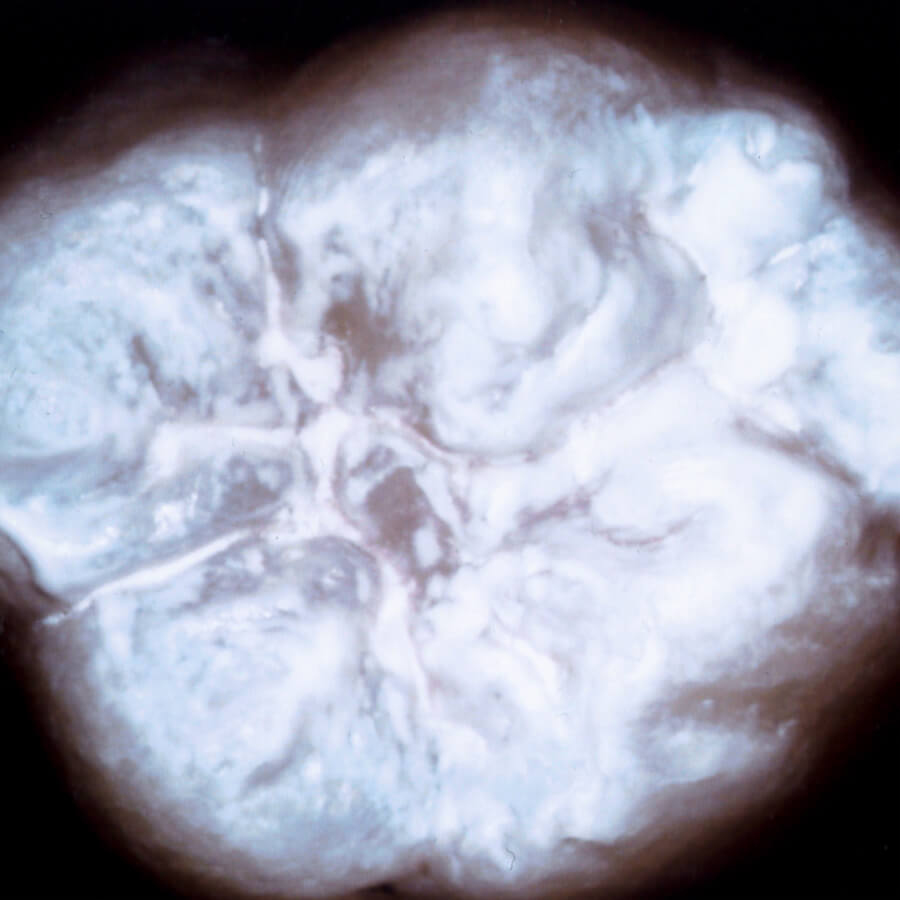

この画像は左は未処理のもの、右は人工エナメル質処理を施した天然歯を撮影したものです。

未処理

小臼歯

大臼歯

人工エナメル質処理

回人工エナメル質処理を行なった歯の画像